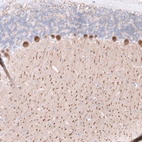

Immunohistochemistry analysis in human kidney and prostate tissues using AMAb92006 antibody. Corresponding CALB1 RNA-seq data are presented for the same tissues.